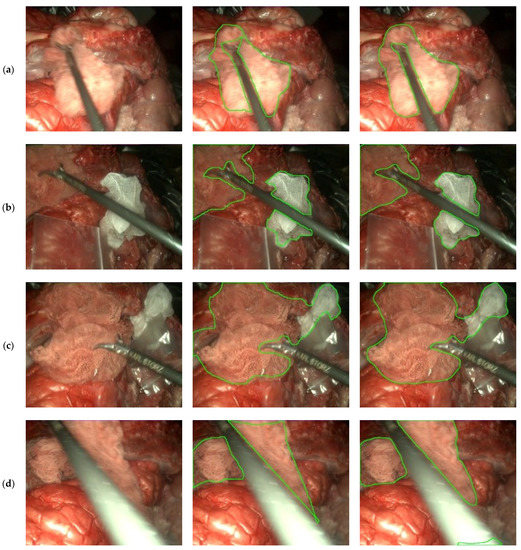

3.3. Gauze Segmentation